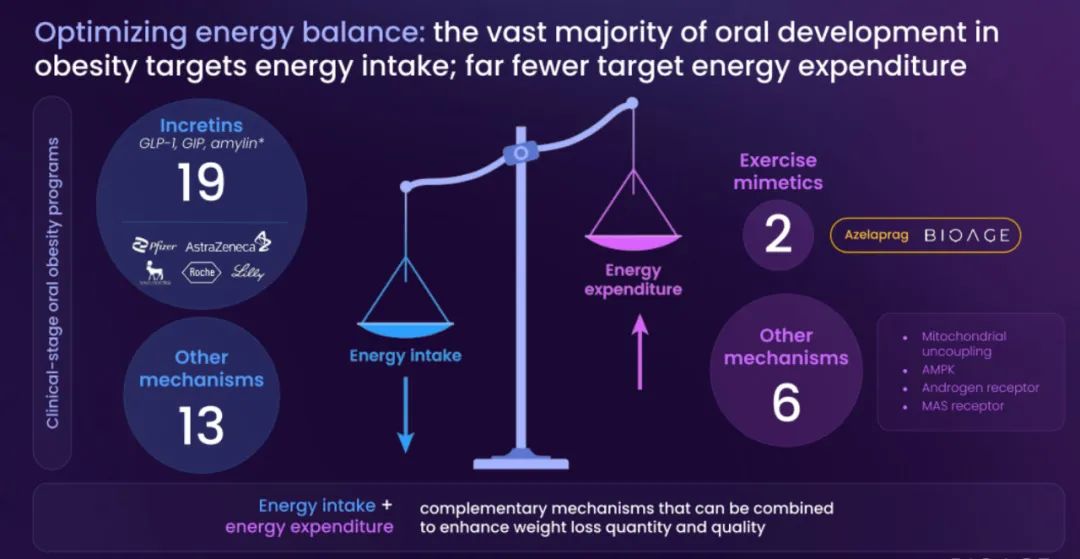

BioAge Labs是一家临床阶段的生物制药公司,致力于针对人类衰老生物学,开发肥胖等代谢疾病的治疗产品候选物。

BioAge Labs的主要关注点是代谢疾病,这是全球最大的医疗保健挑战之一。BioAge Labs的主要候选产品 Azelaprag是一种口服小分子,在8个 1 期临床试验中,265 名受试者的耐受性良好。在临床前肥胖模型中,azelaprag 显示出能够使胰高血糖素样肽-1 受体 (GLP-1R) 激动剂诱导的体重减轻增加一倍以上,同时恢复健康的身体成分并改善肌肉功能。

BioAge Labs正在进行的 STRIDES 临床试验将评估阿泽拉普拉格与礼来公司 (Lilly) 以 Zepbound® 为商品名销售的替泽帕肽联合使用的效果,预计在 2025 年第三季度公布顶线结果。第二项 2 期临床试验将评估阿泽拉普拉格与诺和诺德以 Wegovy® 为商品名销售的索马鲁肽联合使用的效果,预计在 2025 年上半年启动。